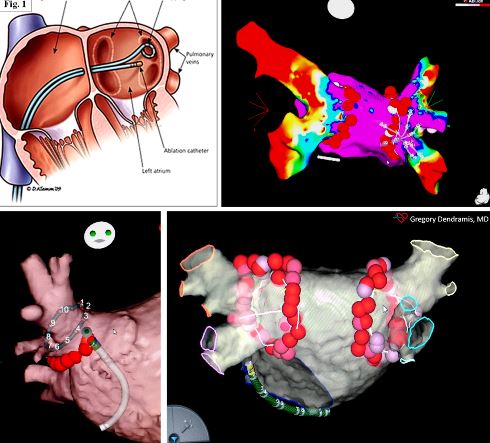

Dal punto di vista puramente tecnico l’ablazione della fibrillazione atriale ha come obiettivo principale l’isolamento elettrico delle vene polmonari che può essere ottenuto con metodiche ablative differenti ed utilizzando principalmente due forme di energia, la radiofrequenza o la crioenergia.

Figura 1

Le lesioni eseguite durante la procedura ablativa possono essere effettuate punto a punto “point-by-point” con l’ausilio di sistemi di mappaggio elettroanatomico prevalentemente mediante erogazione di radiofrequenza (fig. 1) o con metodiche a singolo colpo “one shot” con erogazione di crioenergia (fig. 2) o a breve anche con utilizzo di radiofrequenza.

Ad oggi le più utilizzate sono costituite dall’utilizzo di un catetere multielettrodo con erogazione di radiofrequenza bifasica o da un catetere con pallone che posizionato in maniera occludente a livello della vena eroga crioenergia determinando la necrosi del tessuto ed il conseguente isolamento e blocco elettrico bidirezionale delle vene polmonari aritmogene.